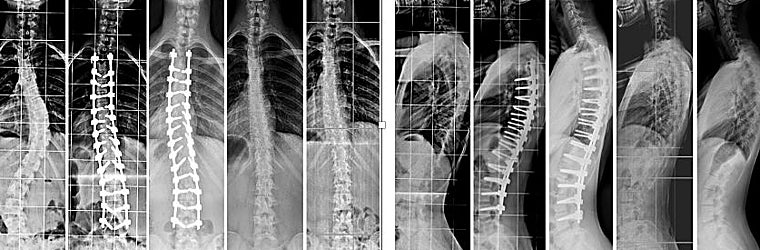

Método único e innovador para tratar la escoliosis en adolescentes: Guide Posterior Vertebral Modulation-GPVM

La innovadora técnica desarrollada por el Dr. Jesus Burgos ofrece un nuevo enfoque para el tratamiento de la escoliosis en adolescentes

La GVPM corrige completamente la deformidad estética, optimiza la capacidad respiratoria, evita el riesgo de degeneración de los discos y preserva la movilidad de la columna vertebral, sin dejar implantes metálicos permanentes.